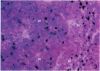

The localization of intravenously injected labelled syngeneic lymphoid cells was studied in the spleen of mice and compared with the localization of Indian-ink-containing macrophages. To distinguish between Indian-ink-containing lysosomes of macrophages and silver grains formed in the autoradiographs over the radiolabelled cells, the latter grains were stained blue by a colour-coupling process. Labelled cells were injected 2 h after the Indian ink. Two hours after their injection the bulk of the labelled cells in the spleen was already localized in the white pulp. At this time the Indian ink had been ingested by macrophages in the marginal zone and to a somewhat lesser extent in the red pulp. Twenty-four hours after injection of the cells their concentration in the white pulp appeared constant or had decreased markedly, dependent on the source of the injected cells (spleen, lymph nodes or thymus). At this time carbon-containing macrophages were also found in the white pulp although they contained less carbon than macrophages in the marginal zone and red pulp. A positive correlation between labelled cells and carbon-containing macrophages was never seen in any part of the spleen. It is concluded that, if carbon-containing macrophages induce lymphocyte trapping, as has been supposed by other authors, this trapping must be mediated by the macrophages in an indirect way, e.g. by soluble mediator molecules released in the circulation.